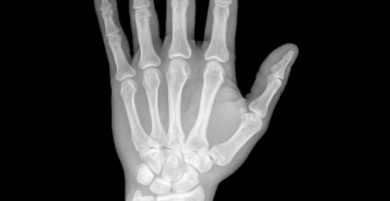

L’arthrite rhumatoïde est causée par une inflammation au niveau des tissus et des articulations.

Voilà pourquoi les rotules éprouvent une grosse difficulté lors d’un mouvement. Il s’agit d’une maladie auto-immune, ce qui veut dire que l’organisme s’attaque lui-même par erreur.

Ils ressentent également une intense chaleur, des gonflements et une déformation des articulations, en plus d’un engourdissement des mains et des pieds et d’autres maladies comme celle du syndrome de l’œil sec.